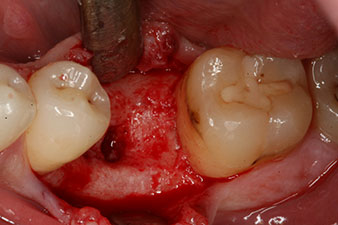

El torque en el momento de la carga mecánica fue de 43 Ncm. Asimismo, después de atornillar un poste de medición especial adaptado al sistema de implante (SmartPeg), el valor ISQ se determinó con la sonda del módulo Osstell ISQ de W&H.

Este habría permitido una cicatrización abierta o incluso un tratamiento inmediato. Sin embargo, como no se disponía de suficiente hueso en la parte crestal del implante, el área se aumentó con las virutas óseas recopiladas durante la preparación del lecho del implante y se suturó para que no penetrara saliva.